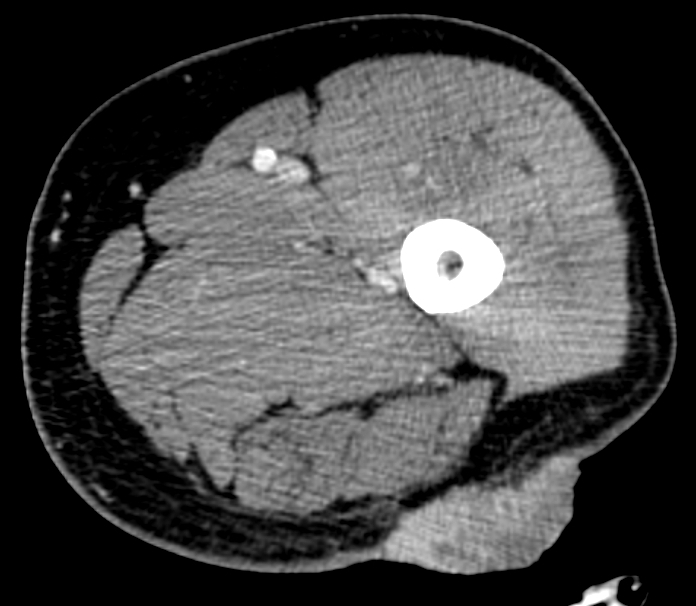

The patient underwent staging with whole-body, contrast-enhanced computed tomography (CT). CT confirmed the thigh lesion and the lymph-node metastasis but allowed to rule out any distant metastasis. The patient underwent successfully surgery, with wide excision of the primary thigh tumor and with left groin radical lymphadenectomy. The patient is now free of recurrence at two years from surgery.

figure 4. Cytology (Papanicolaou coloration) and immunocytology (CD56 marker) of the inguinal lymph-node showing MCC metastasis. figure 5. Contrast-enhanced CT scans showing left inguinal region lymph-node metastasis (a, arrow) and left thigh cutaneous nodule (b).